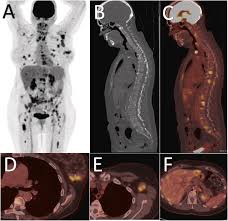

An FDG PET CT scan uses a glucose-based radioactive tracer called FDG. Since cancer cells, infections, and inflammatory tissues consume more glucose than normal cells, this scan highlights abnormal metabolic activity in the body. The Best FDG PET CT Scan in HauzKhas helps doctors detect diseases that may not be visible on routine CT or MRI scans.

Cancer detection and staging

Monitoring response to chemotherapy or radiation

Detecting cancer recurrence

Evaluating unexplained fever or weight loss

Identifying infections and inflammatory conditions